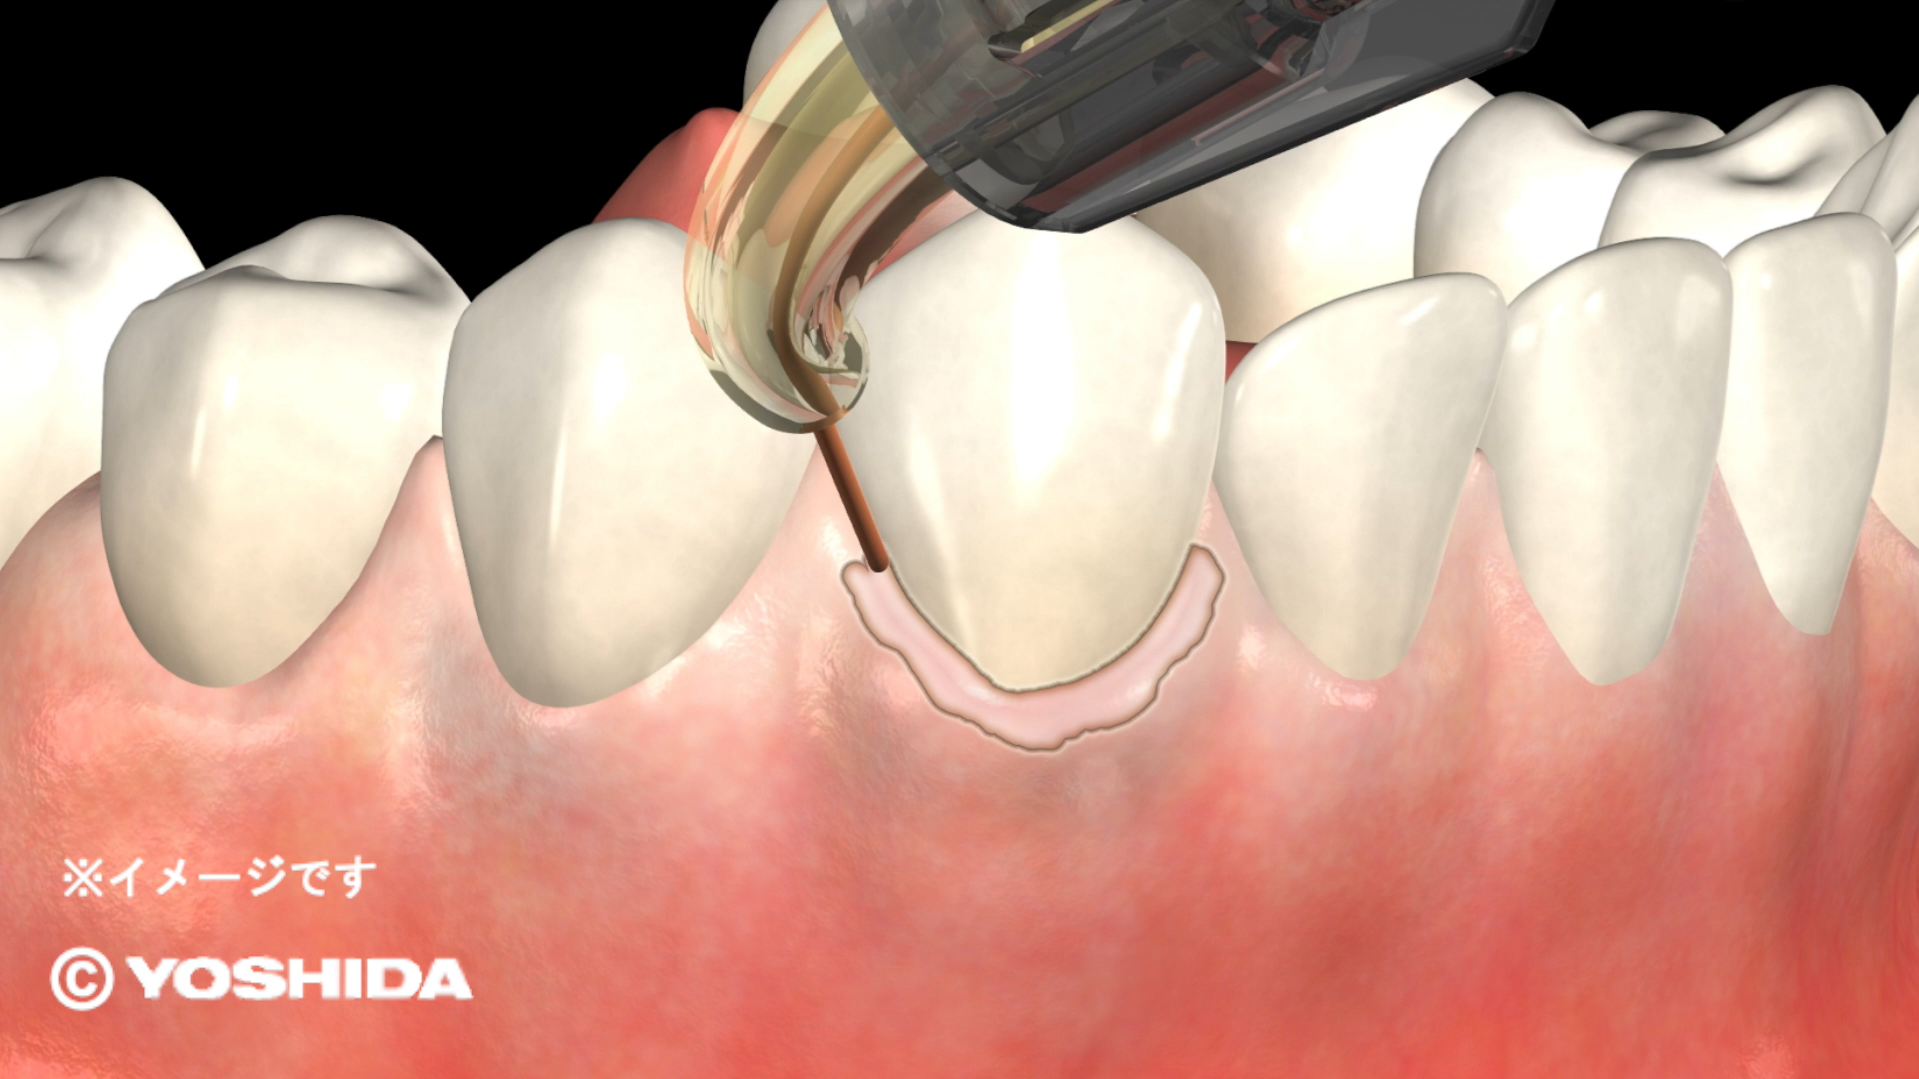

(1)オペレーザー商品とは、株式会社吉田製作所が製造する歯科用レーザー機器であって、「オペレーザー」を販売名に含む商品をいいます。